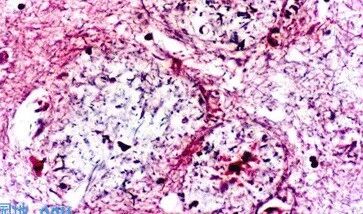

Mallory染色,显示胶原纤维,A组排列规则